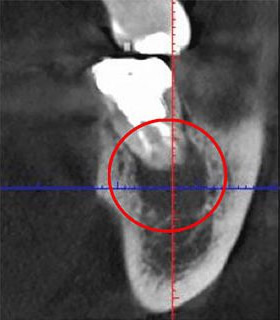

実際に根管の画像をご覧ください。歯の中に存在する黒い筋が、これが根管です。

根管は非常に複雑な形状をしており、特に狭い部分では直径が1mmにも満たないことがあります。このような繊細な根管から、感染した組織を完全に除去するのは容易ではありません。しかし、多くの歯科医院ではこの作業を肉眼で行っているため、どうしても限界があります。その結果、日本の根管治療の成功率が低い原因の一つとも言われています。

歯の内部にある根管は、肉眼で見えないため、その形状を把握するためにはX線検査が欠かせません。従来は「レントゲン」が一般的でしたが、当院ではより精密な検査を可能にする「CT」を用いています。レントゲンが2次元での撮影に限られるのに対し、CTはお口の周囲を回転しながら撮影することで、立体的で鮮明な画像を提供します。

以下の画像は、同じ部位をCTとレントゲンで撮影したものです。

左がCTによる撮影、右がレントゲンによるものです。赤丸で示された黒い影は炎症を示しています。しかし、右のレントゲン写真ではこの影が見えません。

このことからもわかるように、レントゲン写真だけに頼った診断では、こうした炎症が見逃される恐れがあります。炎症が進行すると、最悪の場合、抜歯が必要となる可能性もあります。当院では、こうしたリスクを未然に防ぐため、CTによる詳細な診断を心掛けています。